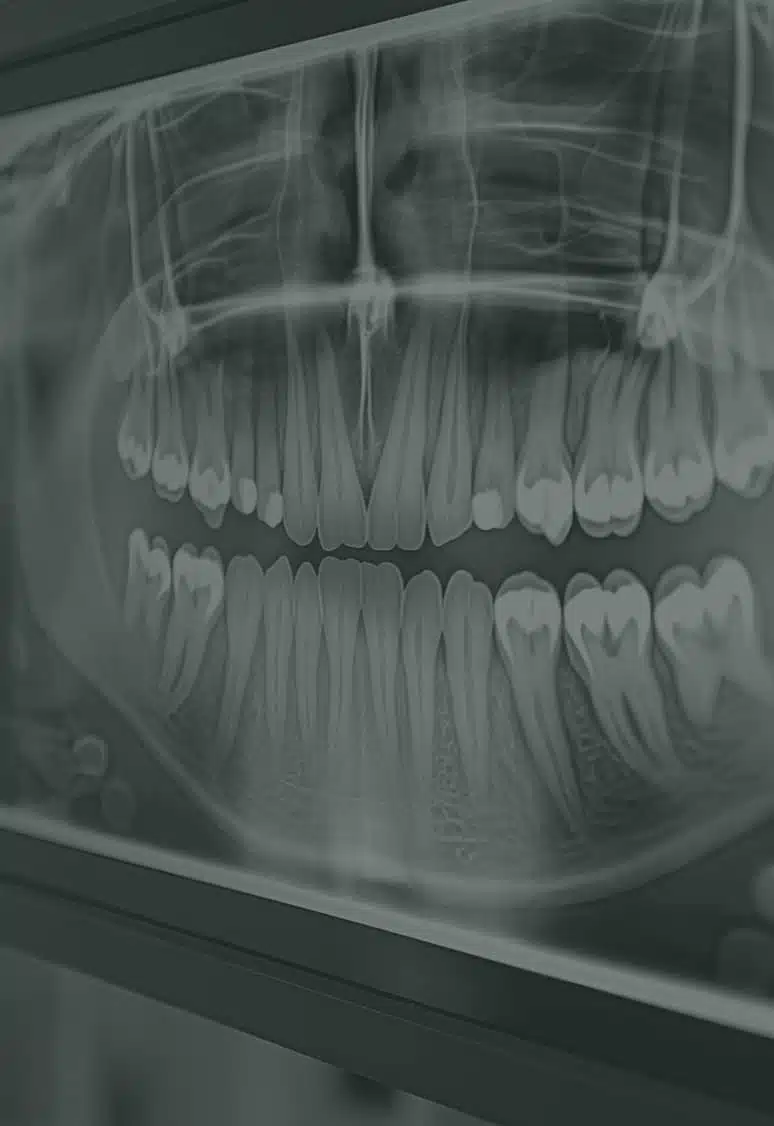

Cette intervention est souvent pratiquée de façon préventive, chez les patients jeunes ayant déjà suivi un traitement orthodontique. Un panoramique dentaire permettra de juger de la forme des germes et du manque de place. L’objectif étant d’éviter que l’éruption des ces dents de sagesse ne viennent dérégler l’alignement dentaire obtenu par le traitement orthodontique.

Avant l’extraction, votre chirurgien maxillo-facial effectuera en consultation une évaluation complète de votre santé bucco-dentaire, incluant des radiographies (panoramique dentaire) pour évaluer la position des dents de sagesse et détecter d’éventuelles complications. Vous déciderez alors avec votre chirurgien des modalités de l’anesthésie, locale ou générale.